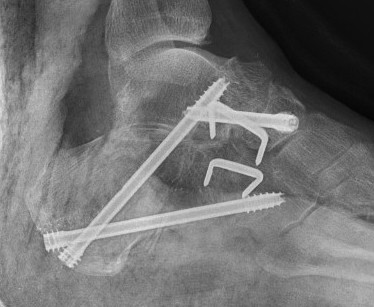

Open Middle Talocalcaneal bar resection +/- calcaneal lengthening osteotomy

+/- calcaneal lenthening osteotomy

- use bone resected from coalition

- K wire to stabilize calcaneocuboid joint